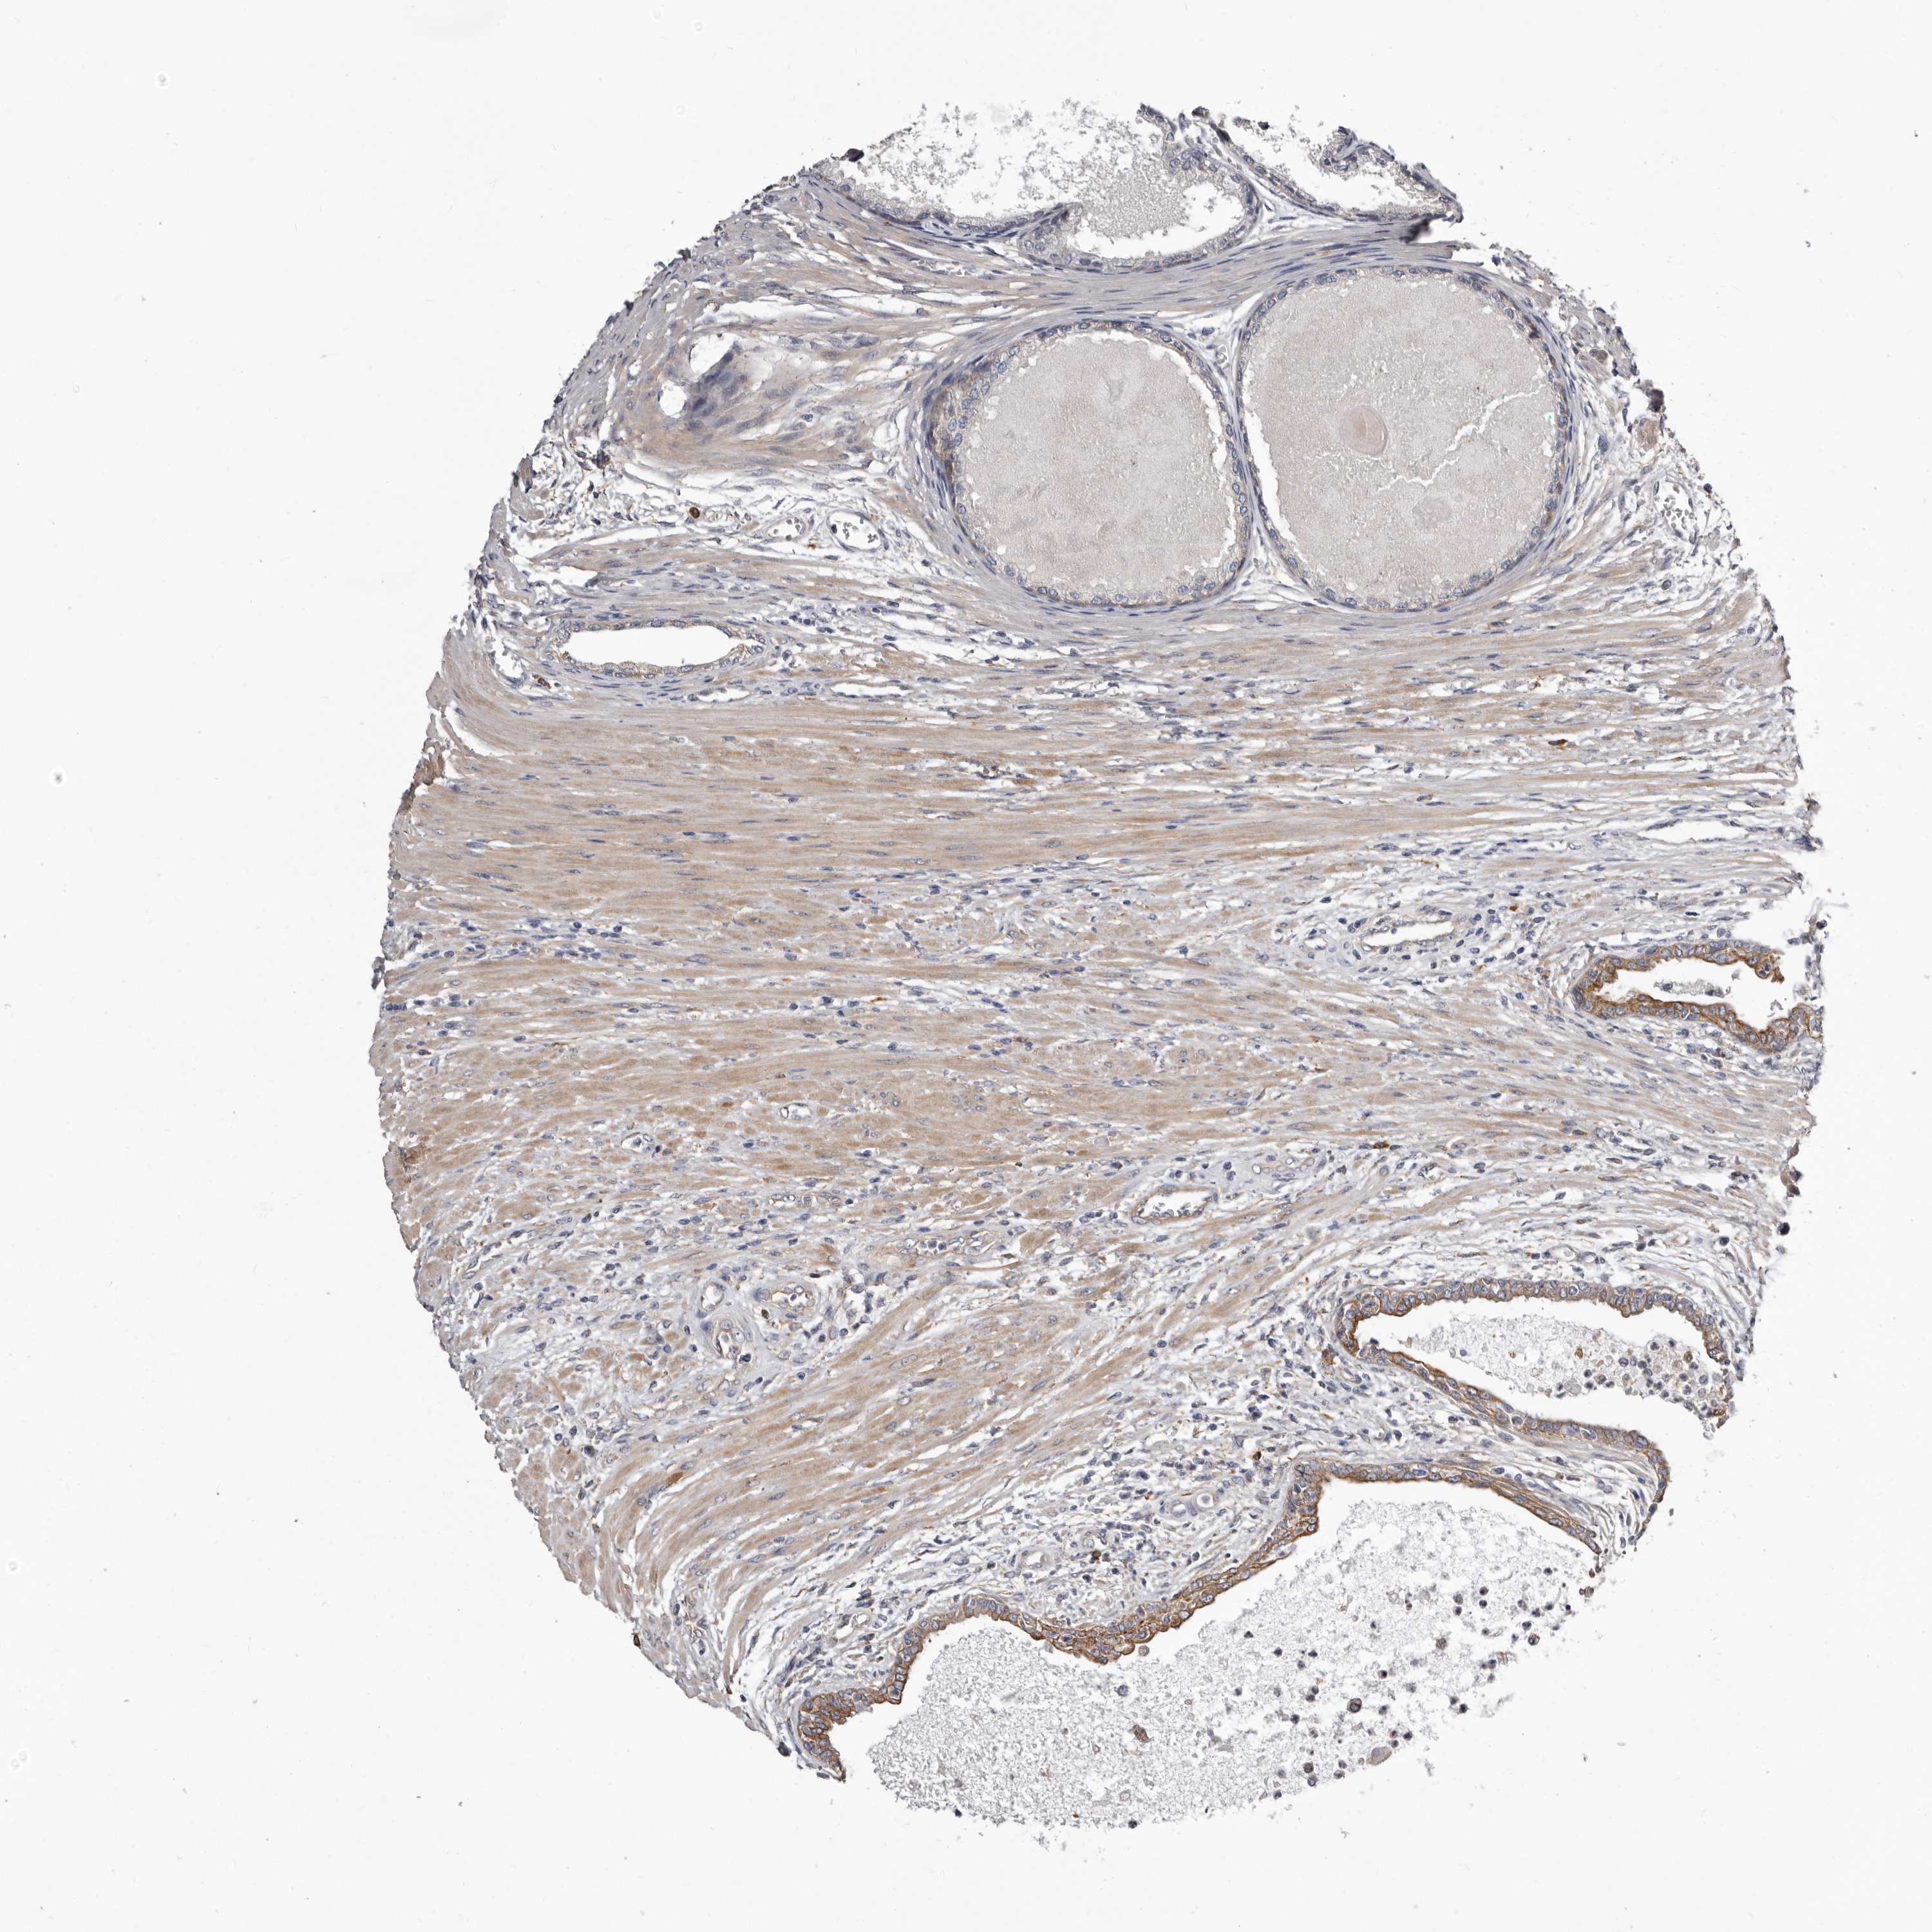

PROSTATE CANCER - Protein expressioni

A mouse-over function shows sample information and annotation data. Click on an image to view it in a full screen mode. Samples can be filtered based on level of antibody staining by selecting one or several of the following categories: high, medium, low and not detected. The assay and annotation is described here.

Antibody stainingi

Antibody staining in the annotated cell types in the current human tissue is reported as not detected, low, medium, or high, based on conventional immunohistochemistry profiling in selected tissues. This score is based on the combination of the staining intensity and fraction of stained cells.

Each image is clickable and will lead to virtual microscopy that enables deeper exploration of all samples and also displays staining intensity scores, fraction scores and subcellular localization as well as patient and tissue information for each sample.

Antibody HPA028448

Antibody HPA028696

Staining

High

Medium

Low

Not detected

Intensity

Strong

Moderate

Weak

Negative

Quantity

>75%

75%-25%

<25%

None

Location

Nuclear

Cytoplasmic/membranous

Cytoplasmic/membranous,nuclear

Adenocarcinoma, High grade

Adenocarcinoma, Low grade

Adenocarcinoma, Medium grade